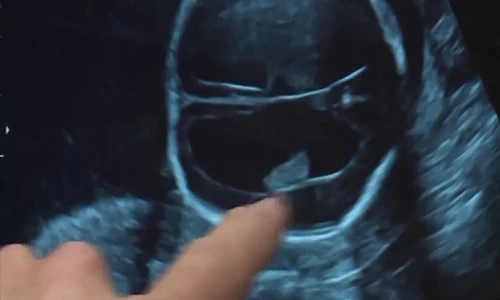

Đưa một thai nhi 19 tuần tuổi ra khỏi bụng mẹ, tiến hành làm phẫu thuật và sau đó đưa bé trở lại bụng mẹ, có lẽ nhiều người đang nghĩ, đây là một câu chuyện hoang tưởng, chỉ xuất hiện trên phim ảnh.